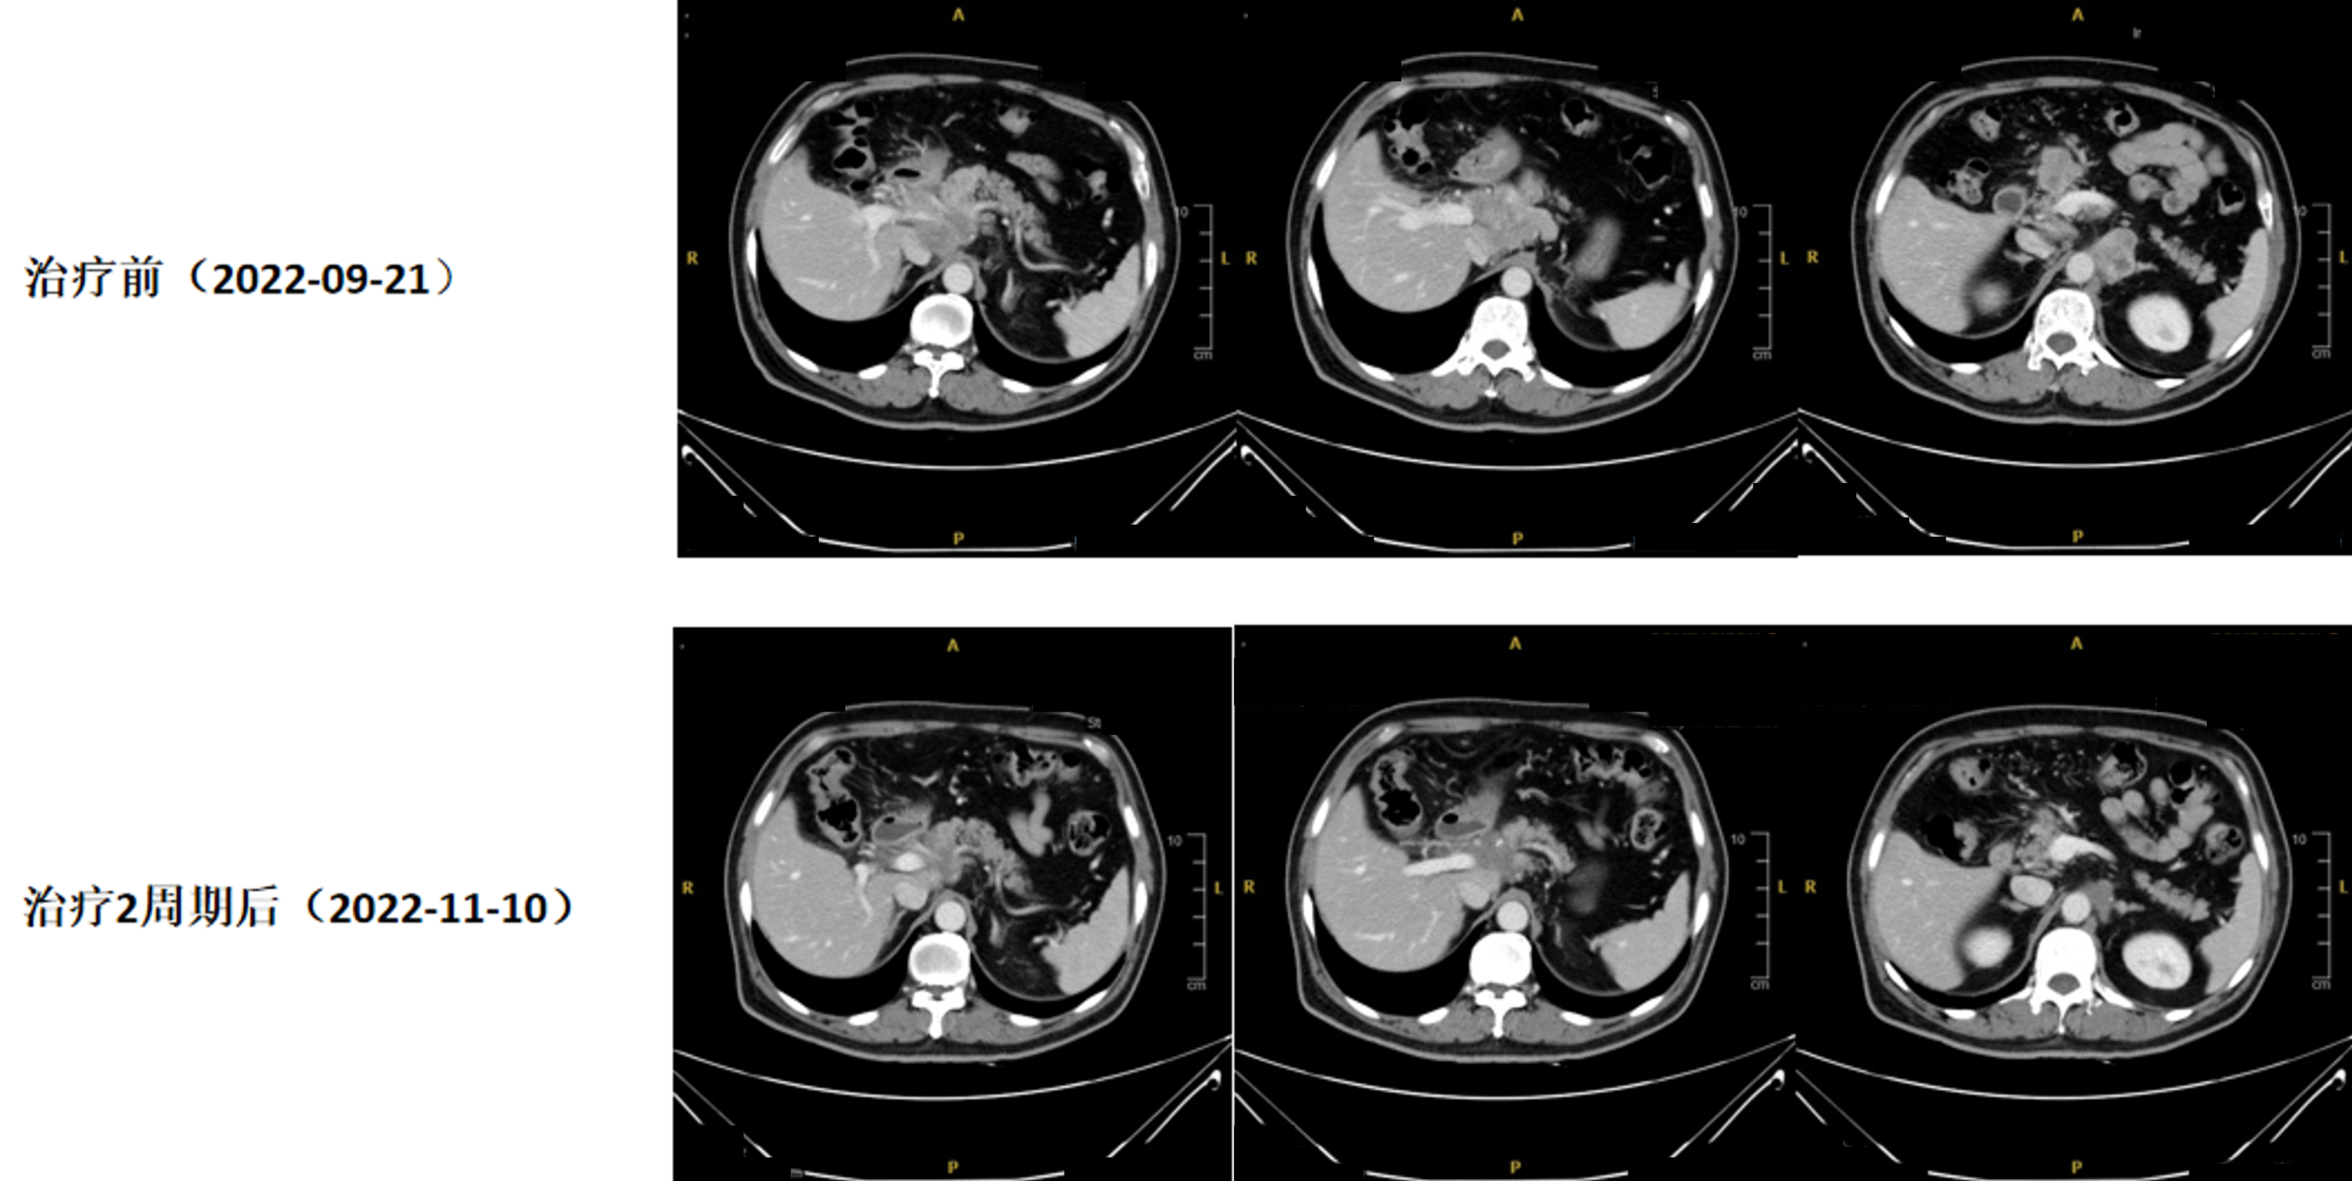

影像学检查(2022年09月21日,胸腹CT:平扫+增强):胰腺颈部占位,考虑为胰腺癌伴瘤周、肝门区、肠系膜根部、腹腔动脉根部、腹膜后多发淋巴结转移可能。胃窦黏膜稍增厚。

图1. 2022年09月21日 初诊腹部CT影像

2周期治疗后疗效评估(CT复查:2022年11月10日): 胃窦病灶较前好转。胰腺颈部病灶较前退缩,肝门区、肠系膜根部、腹腔动脉根部、腹膜后多发转移淋巴结较前缩小。

图2. 治疗前(2022年09月21日)与治疗2周期后(2022年11月10日)CT对比

放疗后疗效评估(CT复查:2023年06月27日): 胃窦壁稍显增厚,目前病灶显示不明确,较2022年09月21日首诊片好转;腹腔及腹膜后多发肿大淋巴结,大部分较前变化不大,个别较前缩小,原胰腺颈部病灶目前轮廓显示不明确,局部密度稍显致密。

图6. 治疗8周期后放疗前(2023年04月06日)与放疗后(2023年06月27日)CT对比

定期影像评估,至2025年03月03日病情稳定。

CT复查(2025年03月03日):胃窦壁局部稍显增厚,黏膜面强化尚可,较前变化不大;胰颈软组织肿块目前轮廓显示仍不明确,局部稍显致密;瘤旁、肝门区、肠系膜根部多发肿大淋巴结较前大致相仿。

图7. 首治前(2022年09月21日)与近期随访(2025年03月03日)CT对比